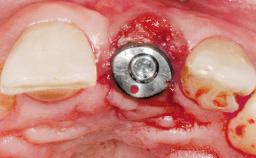

Staged bone augmentation of the alveolar ridge is indicated whenever a proposed implant site is deficient and will not support implant placement with simultaneous grafting. This is particularly true of healed sites presenting with facial flattening of the ridge. Since primary stability cannot possibly be achieved in this situation, it is recommended to use a staged approach with guided bone regeneration (GBR) for correct three-dimensional placement of the implant. In the anterior maxilla, staged GBR procedures are conducted not only to provide adequate bone volume for implant placement but also to restore a proper and stable contour of the orofacial ridge for improved long-term esthetics. A case is presented that demonstrates the technique for single-tooth replacement utilizing a staged approach with a particulate grafting material. A 50-year-old man whose tooth 11 was missing presented for consultation to the Center for Implant Dentistry in January 2010.